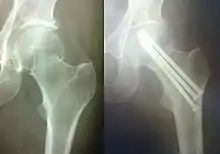

Погружной остеосинтез

Погружной остеосинтез — это оперативное введение фиксатора кости непосредственно в зону перелома. В зависимости от расположения фиксатора по отношению к кости данный метод бывает внутрикостным (интрамедуллярным), накостным и чрескостным. Для внутрикостного остеосинтеза используют различные виды стержней (гвозди, штифты), для накостного — различные пластинки с винтами, шурупами, для чрескостного — винты, спицы. Нередко возможно сочетание этих видов остеосинтеза.

Накостный остеосинтез

Накостный (экстрамедулярный) остеосинтез производят с помощью фиксаторов-пластин различной толщины и формы, соединяемые с костью при помощи шурупов и винтов. Иногда при накостном остеосинтезе в качестве фиксаторов возможно применение металлической проволоки, лент, колец и полуколец, крайне редко — мягкий шовный материал (лавсан, шелк).